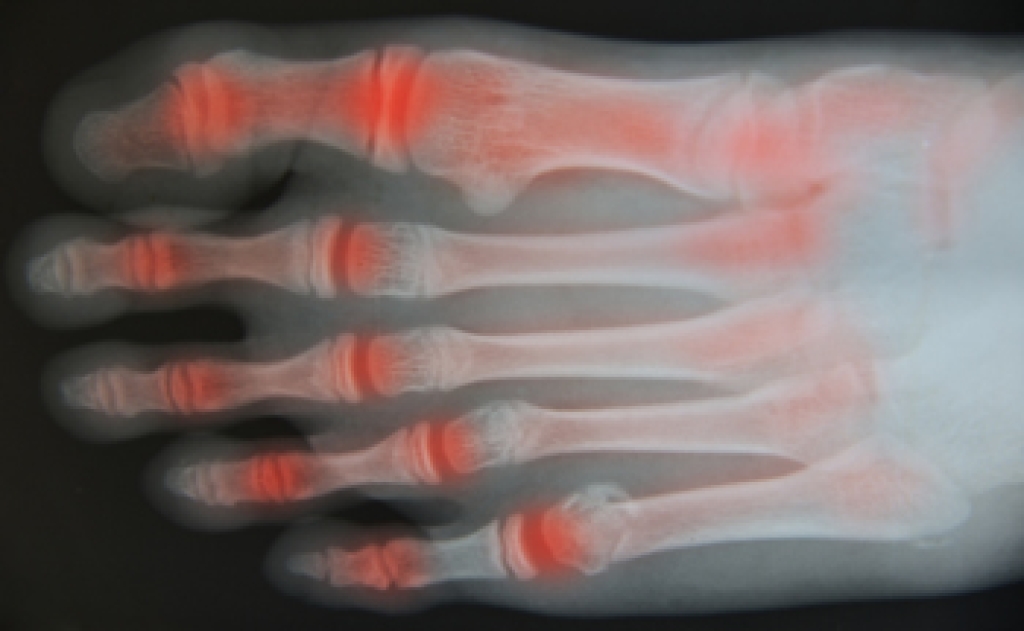

Arthritis, a common condition affecting millions, causes inflammation, stiffness, and pain in the joints. It can make everyday activities challenging and significantly impact quality of life. While there is no cure for arthritis, chiropractic care offers a natural, non-invasive way to manage symptoms and improve joint function.

Chiropractic care can benefit both osteoarthritis and rheumatoid arthritis by focusing on reducing joint strain and promoting better movement.